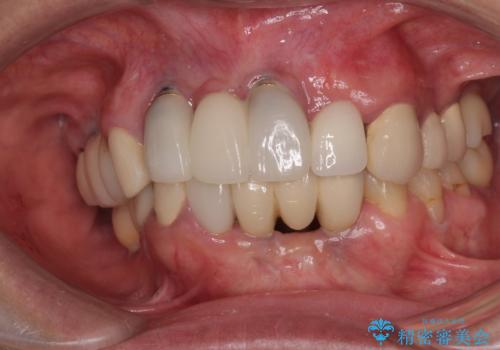

- 以前から頻繁に前歯が土台から外れてしまうことがあり、インプラントによる治療を希望して来院された患者様です。

歯根が割れていることはありませんでしたが、残っている歯質が全て歯肉よりも深い位置にあるため、土台としての機能は不足している状態でした。

歯根周辺の骨や歯肉の状態は良く、抜歯して速やかにインプラントを埋入し、即日で仮歯を装着するプランにて治療を行うこととしました。

初回カウンセリング時にはセラミッククラウンが装着されていましたが、インプラント治療でのご来院時には前歯は外れて紛失をしてしまったとのことでした。

事前に仮歯の型取りをして用意をしていたため、インプラント埋入後に速やかに仮歯を装着しました。

インプラントの安定度も高く、抜歯と埋入から2か月後にはオールセラミッククラウンを装着することができました。